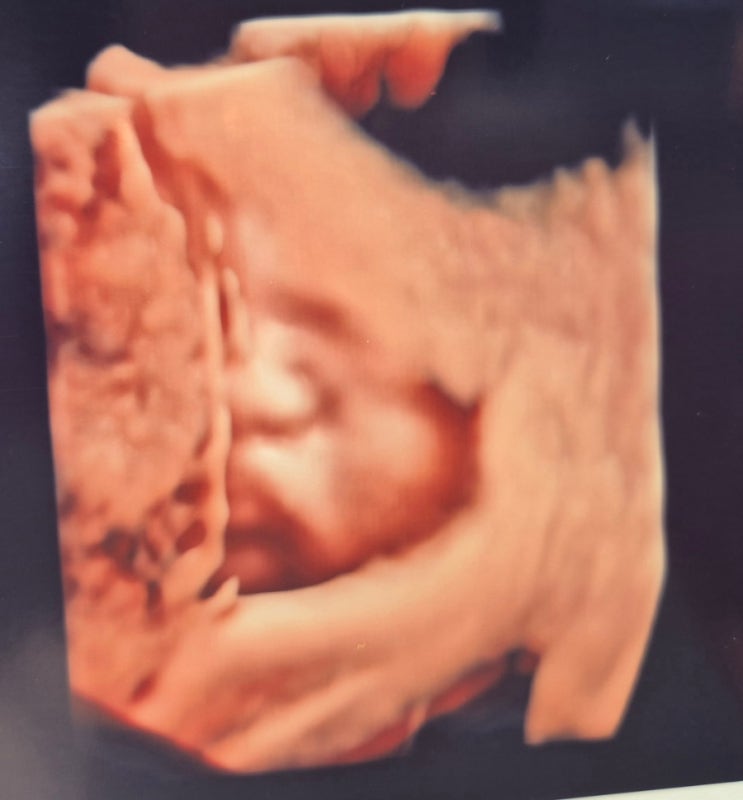

[임신] 31주차 드디어 입체초음파 성공!!! (Feat. 콩콩이 얼굴)

31주차 병원방문 목적은 바로 입체초음파 성공이였어요!!!! 만삭사진 찍어야한단말야ㅠㅠ 얼굴 보여죠 아들...